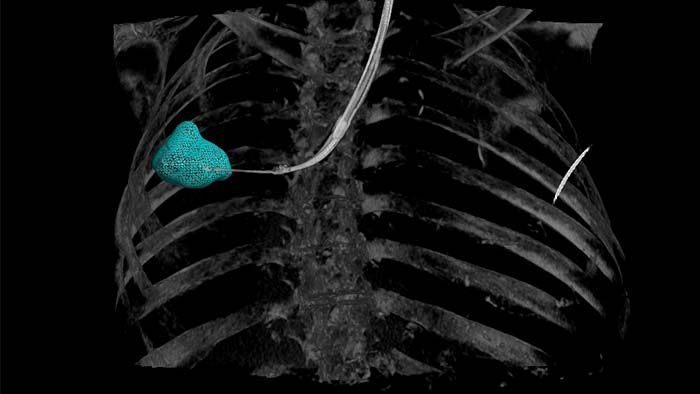

Planning and guidance for percutaneous biopsy, marking and ablative therapy.

with tumor segmentation, 3D navigation support for endobronchial procedures.